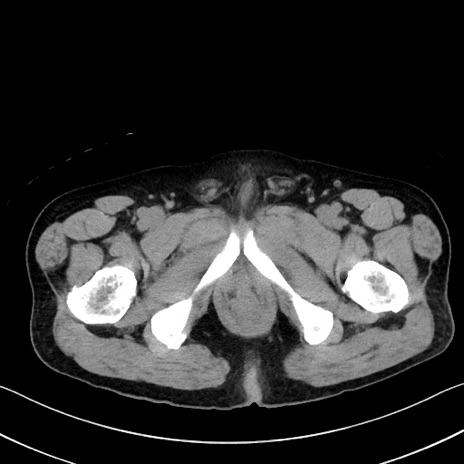

症例35(横断像)

【症例】70歳代 男性

【主訴】腹部膨満、嘔吐

【現病歴】昨日より腹部膨満感出現。本日増悪し、仙痛出現。嘔吐あり、受診。

【既往歴】糖尿病、胆摘後

【身体所見】BP 149/80mmHg、HR 74/min、BT 35.9℃、腹部:膨満、軟、圧痛なし。腸雑音減弱あり。上腹部正中切開瘢痕あり。

【データ】WBC 13500、CRP 1.72